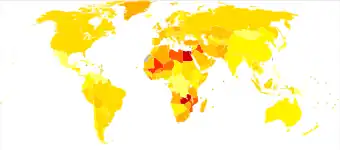

Bladder cancer, as of 2018, affected about 1.6 million people globally with 549,000 new cases and 200,000 deaths.[3] Age of onset is most often between 65 and 84 years of age.[2] Males are more often affected than females.[2] In 2018, the highest rate of bladder cancer occurred in Southern and Western Europe followed by North America with rates of 15, 13, and 12 cases per 100,000 people.[3] The highest rates of bladder cancer deaths were seen in Northern Africa and Western Asia followed by Southern Europe.[3]

Globally, in 2017, bladder cancer resulted in 196,000 deaths, a 5.4% (age adjusted) decrease from 2007.[175] In 2018, the age adjusted rates of new cases of bladder cancer was 6 cases per 100,000 people and age adjusted death rate was 2 deaths per 100,000 people. Lebanon and Greece have the highest rate of new cases. In Lebanon, this high risk is attributed to high number of smokers and petrochemical air pollution.[176]